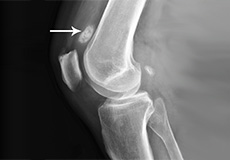

Knee Fracture

A fracture is a condition in which there is a break in the continuity of the bone. In younger individuals, these fractures are caused by high energy injuries, as from a motor vehicle accident. In older people, the most common cause is a weak and fragile bone.